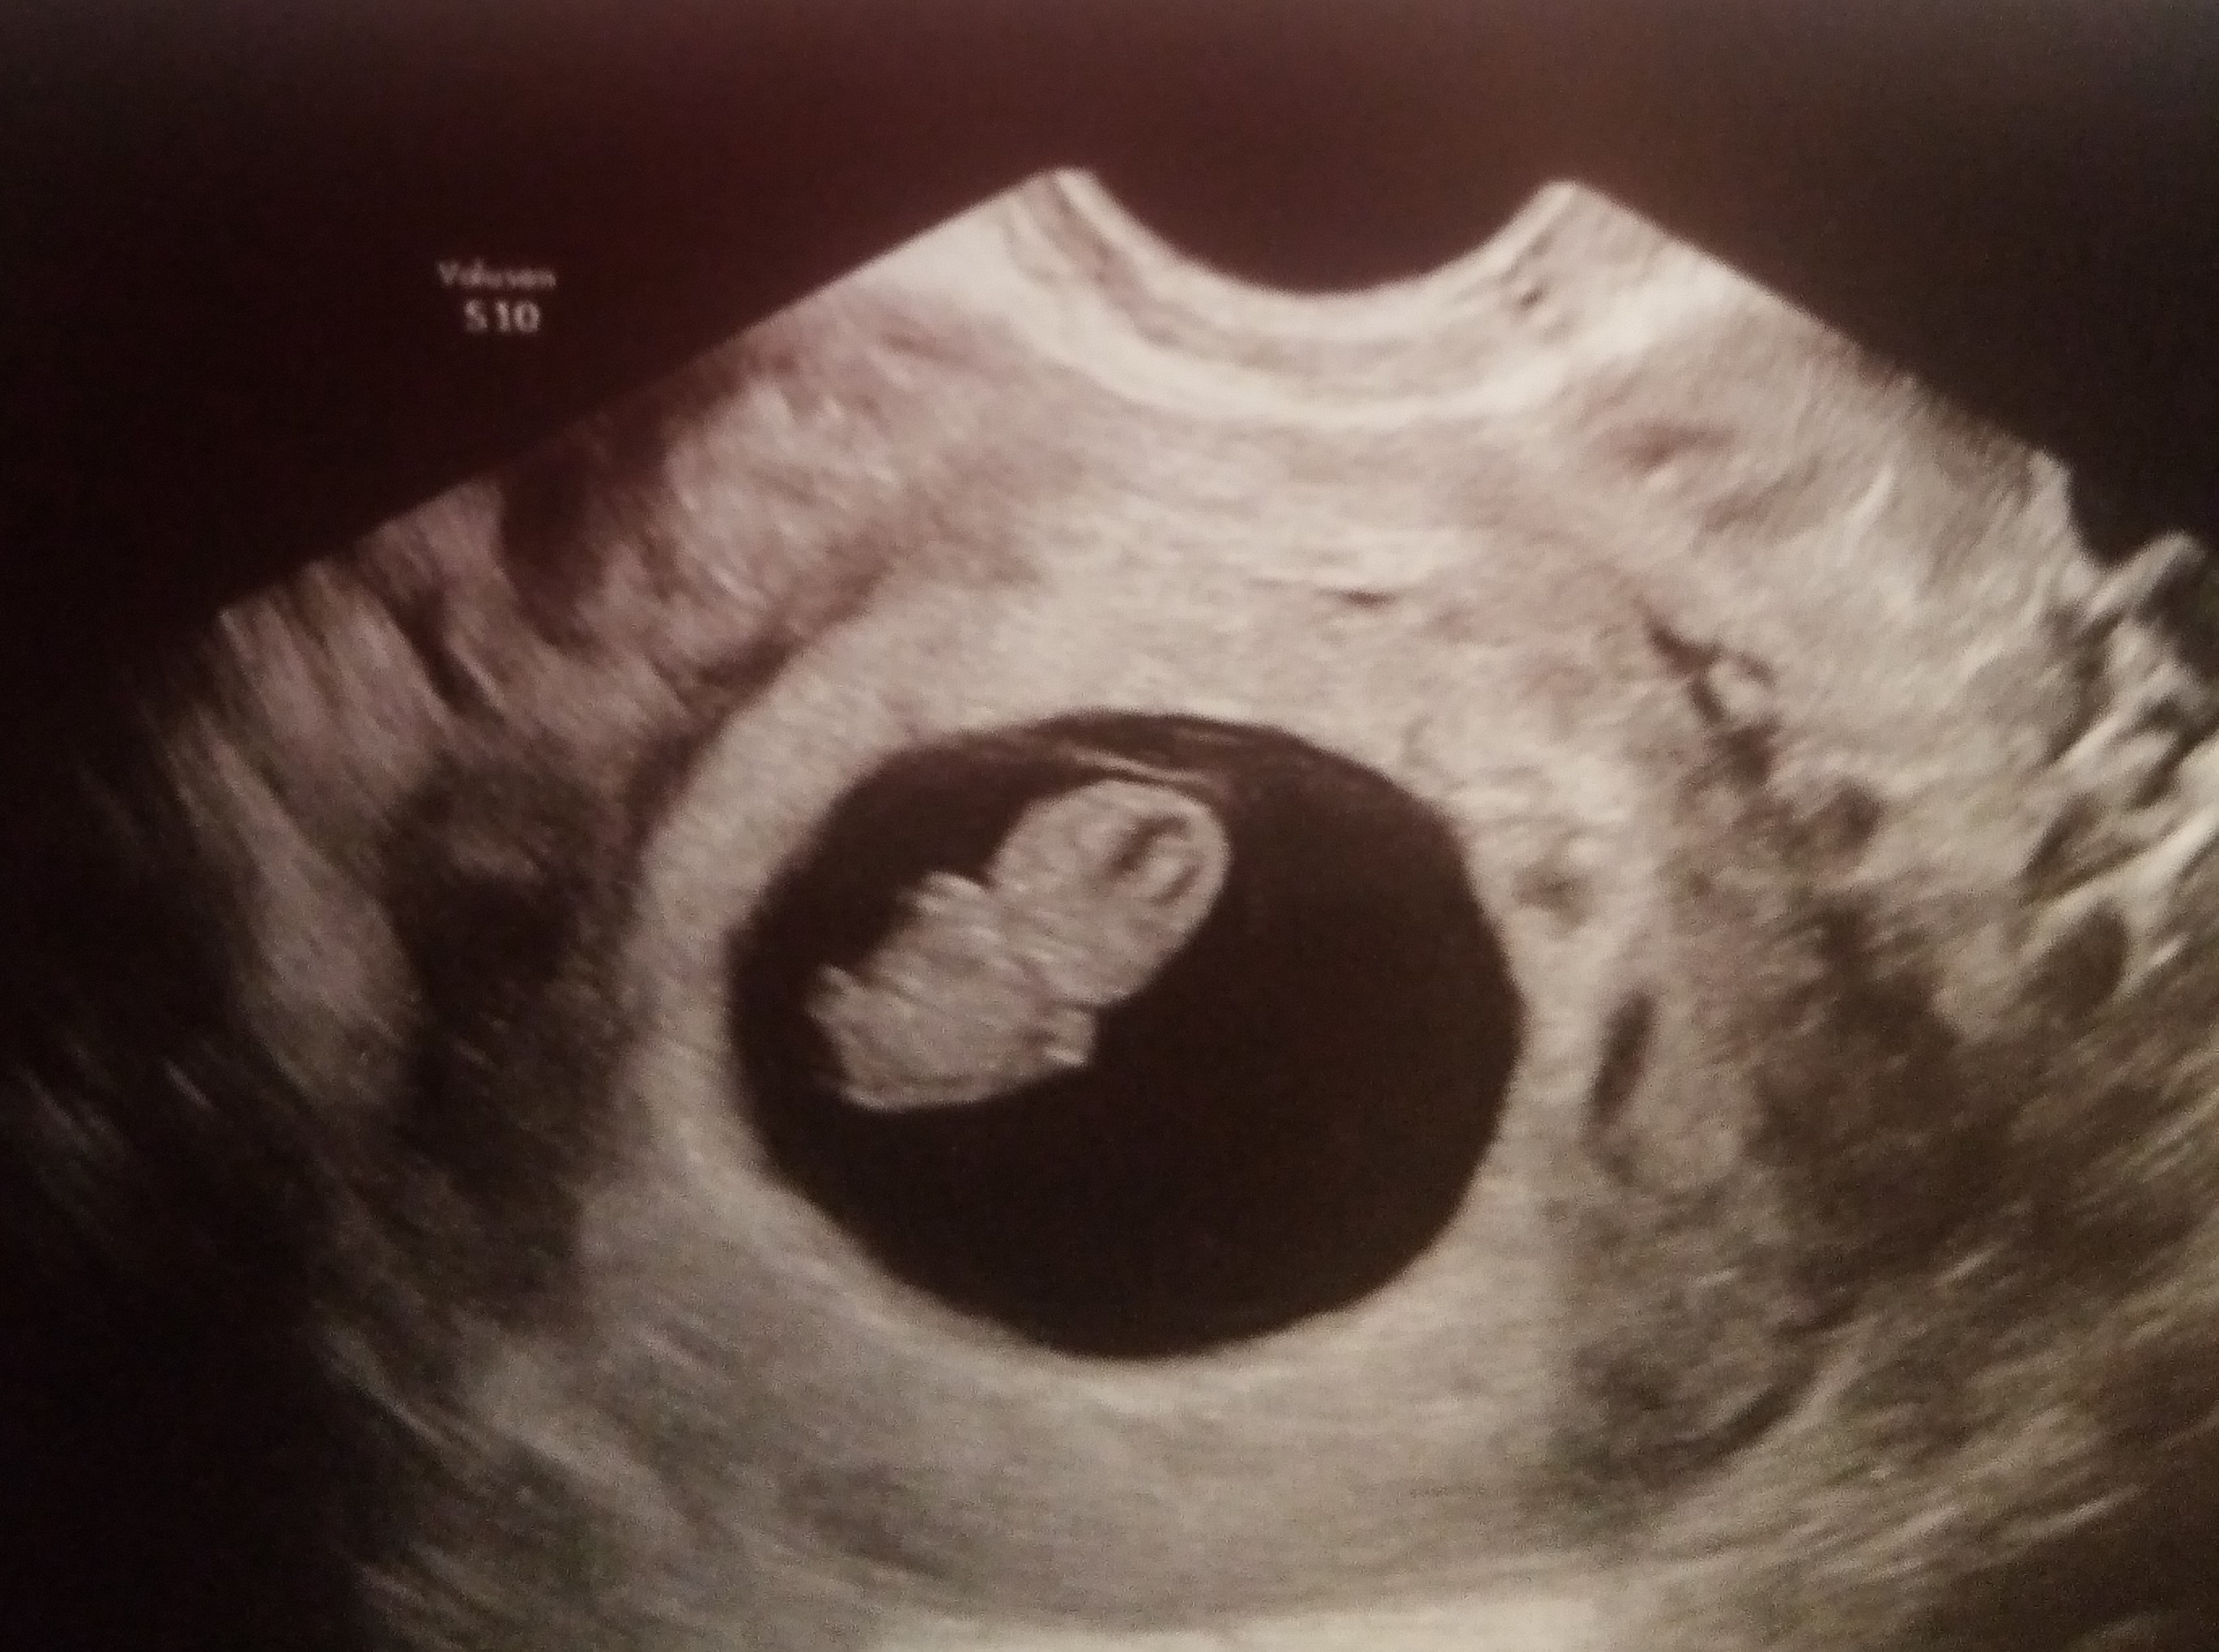

@lepus timidus mikä ihana kuva!!